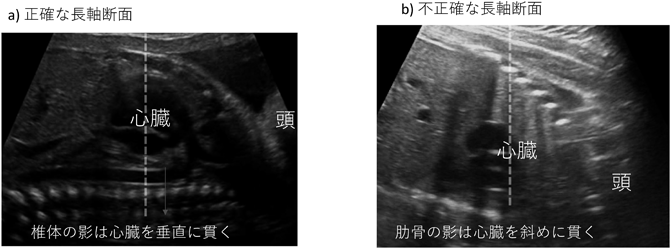

• 胎児の位置を確認したらプローブを母体腹壁に当て,中央に心臓,右に頭となる長軸断面を描出する.ここでのポイントは正確な長軸断面を描出することであり,画面で頭と心臓の深さが同じで,胸郭が画面で水平になること,肋骨または椎体の影が心臓を垂直に貫くことで確認できる(図5).初心者にとって正確な矢状断面の描出は難しく感じるかもしれないが,前述した〈プローブを移動+進行方向のエッジに力を加える〉操作をして正確な長軸断面を描出する.

図5 胎児胸郭の長軸断面と水平断面